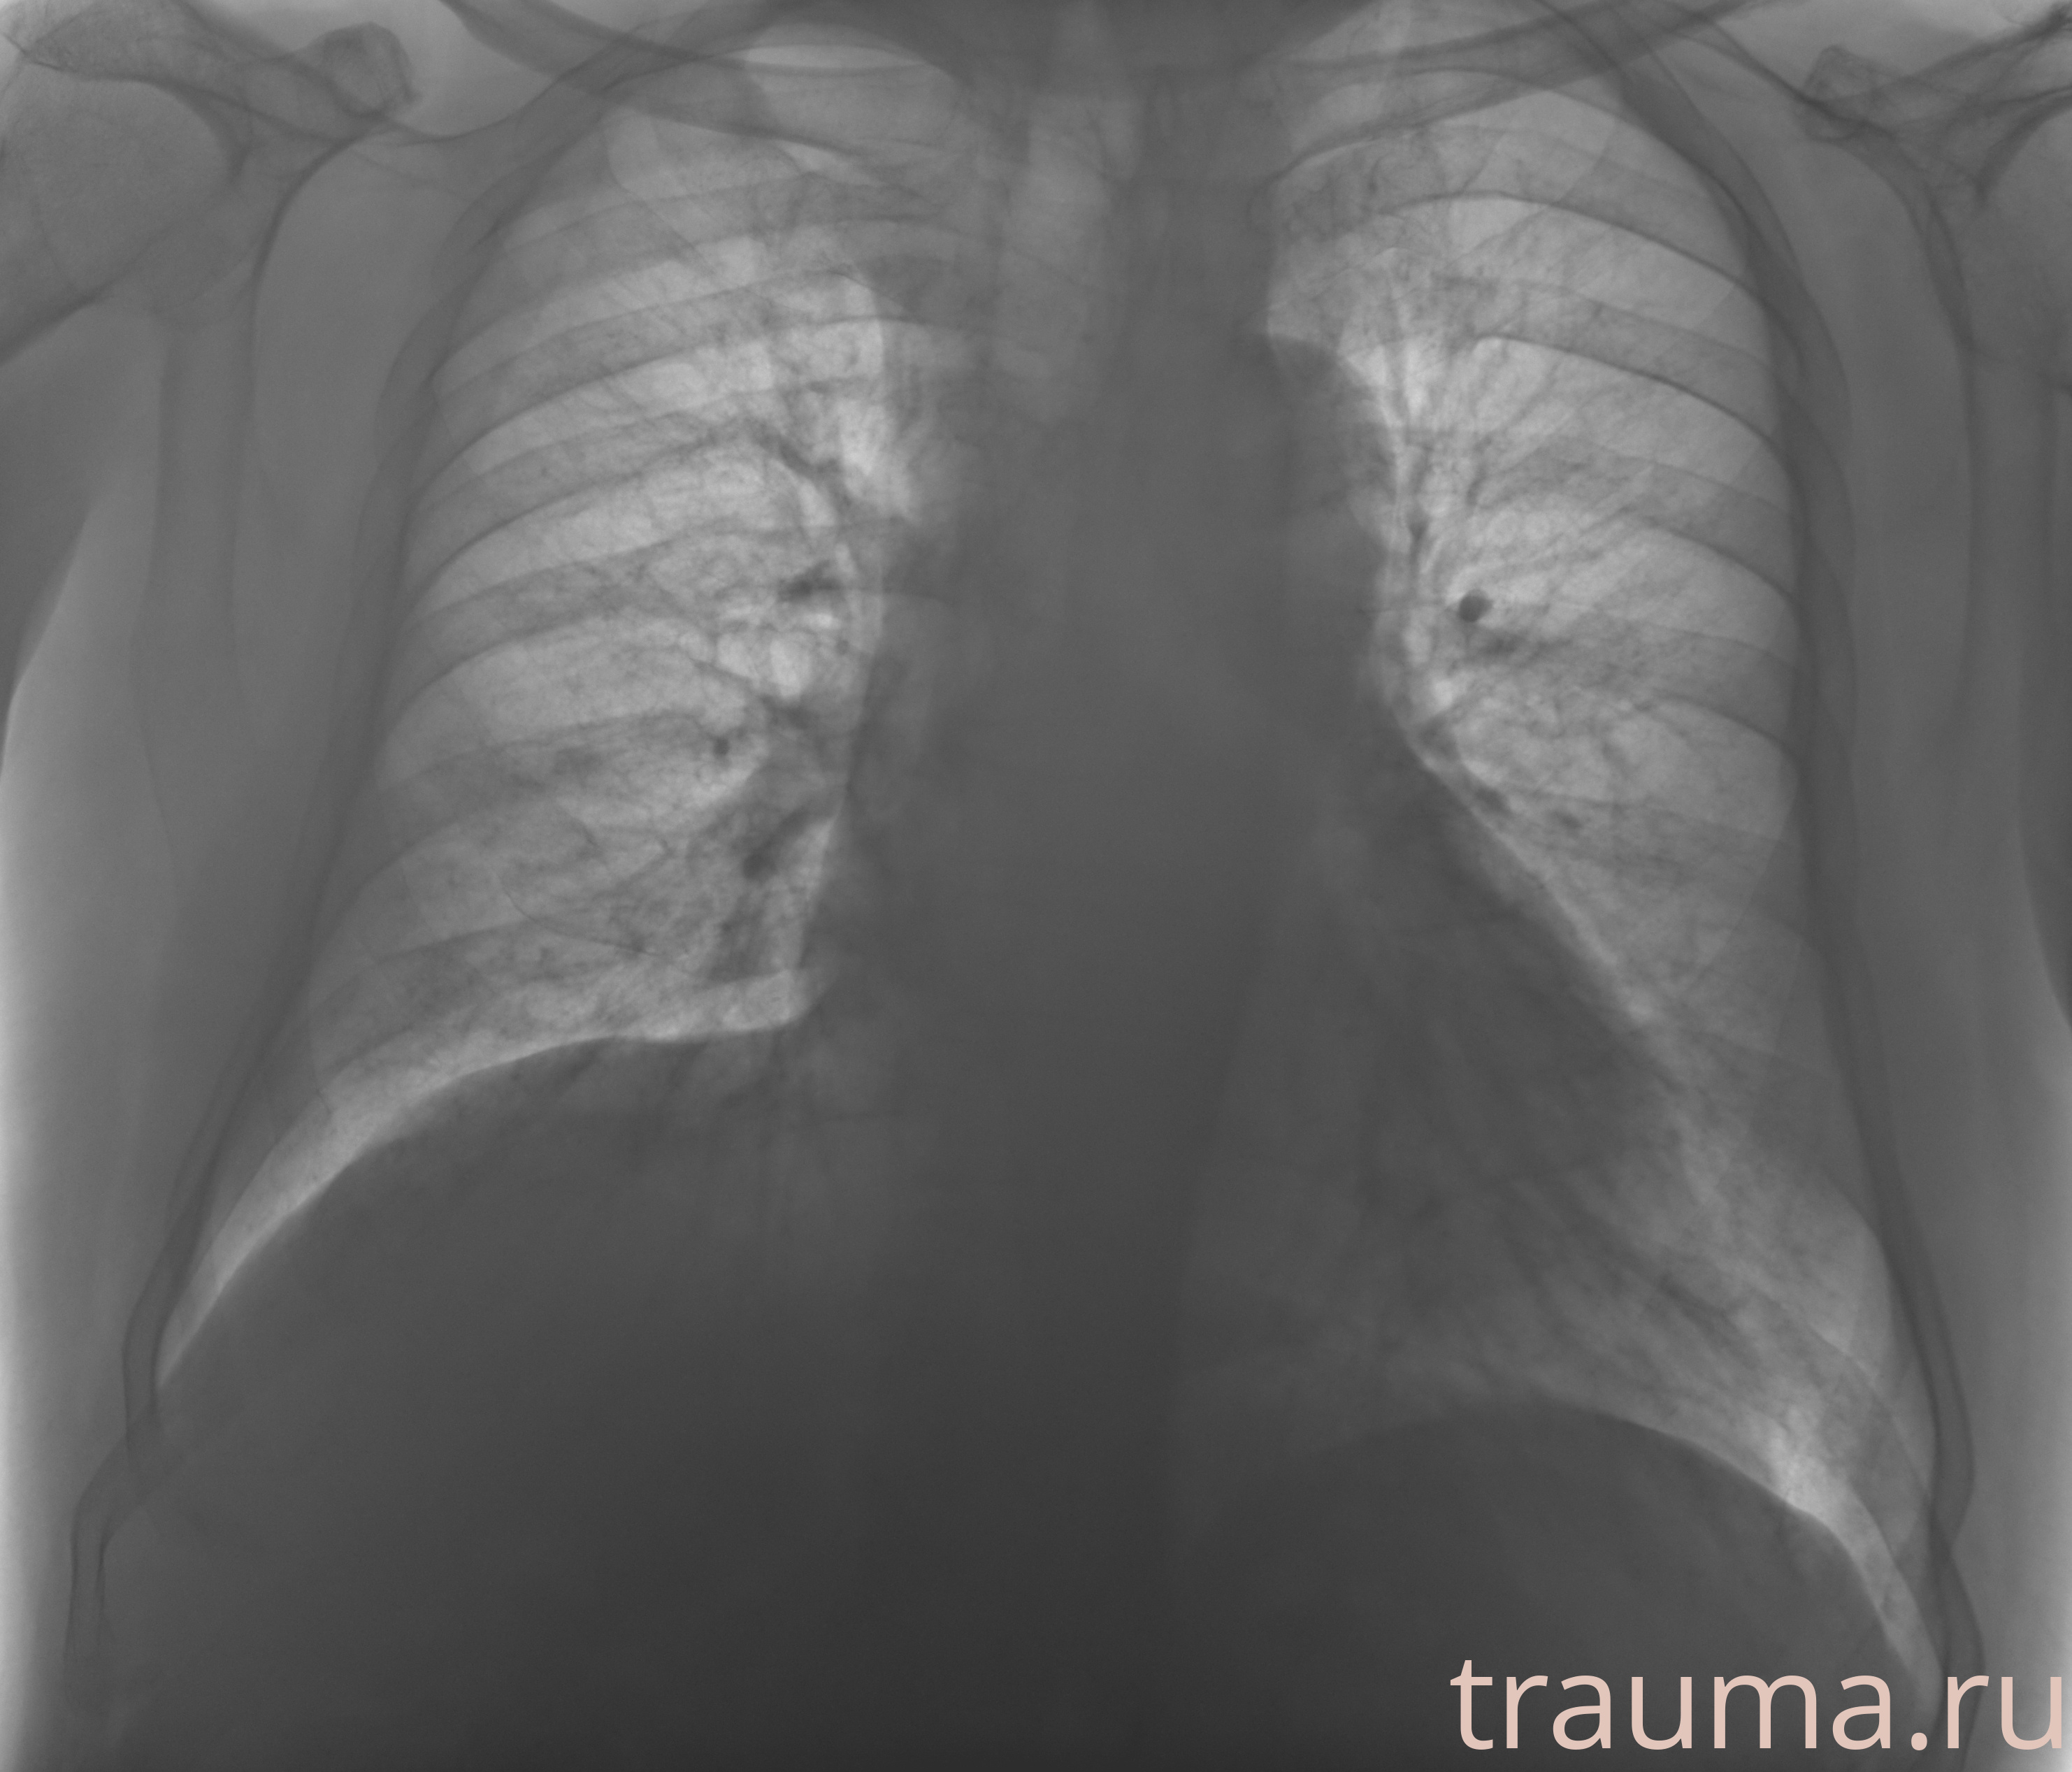

Рентгенограммы

Рентген на дому: по вашему адресу приезжает врач-рентгенолог, травматолог-ортопед с мобильным рентгеновским аппаратом, проводит диагностику травмы или заболевания, делает необходимые рентгенограммы, дает рекомендации по дальнейшему лечению. Получить качественные снимки в домашних условиях возможно благодаря уникальной методике, разработанной МосРентген Центром для института  Склифосовского

при переломе шейки бедра и пневмонии от компании МосРентген Центр - партнера Института имени Склифосовского